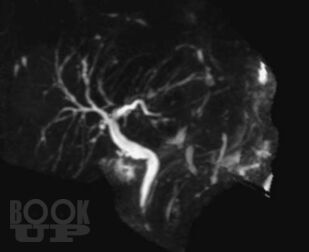

В монографии представлены современные сведения о магнитно-резонансной холангиопанкреатографии (МРХПГ). Детально отражены технические основы метода, методика и планирование исследования. Рассматриваются причины ошибок при интерпретации данных МРХПГ и способы их предотвращения и преодоления. Приведены базовые протоколы различных видов МРХПГ. Описана нормальная анатомия желчевыводящих протоков, желчного пузыря и протоков поджелудочной железы, изменения желчевыводящих протоков, желчного пузыря и протоков поджелудочной железы при патологических процессах. Отражены вопросы диагностики холангиолитиаза и оценки послеоперационной анатомии желчевыводящих протоков. Рассмотрены особенности МРХПГ при патологических изменениях комплекса большого дуоденального сосочка и двенадцатиперстной кишки. Приведены данные о МРХПГ с использованием гепатоспецифического контрастного вещества.